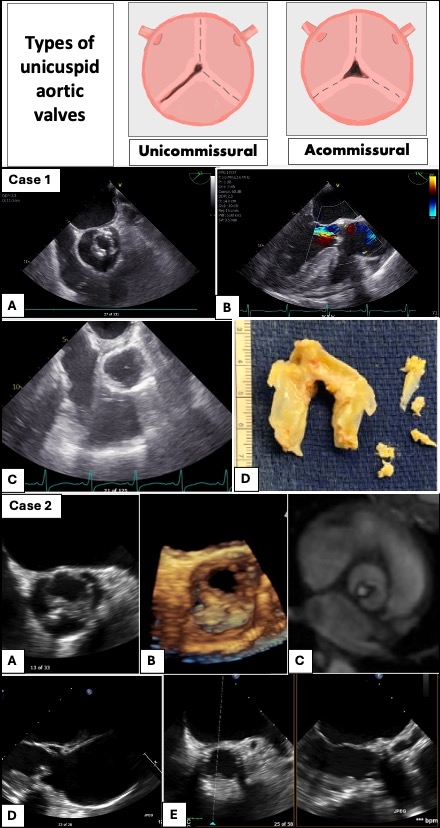

Ross Procedure for Correction of Congenitally Unicuspid Aortic Valve: A Paradigm Shift?

Case 1:

A 54-yr-old man reported exertional dyspnea for 3 months, with a systolic murmur on exam. TTE noted severe aortic stenosis, moderate insufficiency and possible bicuspid valve morphology. Coronary angiogram showed no obstructive disease. CT chest showed a 5-cm ascending aortic aneurysm. CT surgery evaluation was sought, and patient had a Ross procedure with aortic hemiarch repair. Intra-operative TEE confirmed a congenitally unicommissural, unicuspid aortic valve (UAV). A 7-month follow-up TTE showed a normal aortic and pulmonic prosthetic gradient.

Case 2:

A 46-yr-old lady reported progressive exercise intolerance, with a systolic murmur and faint S2 noted on exam. TTE showed severe aortic stenosis. MR angiogram showed a unicuspid valve and a mildly dilated aortic root. The patient was evaluated by CT surgery and underwent Ross procedure. TTE 4 years later showed a normal aortic and a moderately elevated pulmonic prosthetic gradient. Patient continues to exercise without limitations.